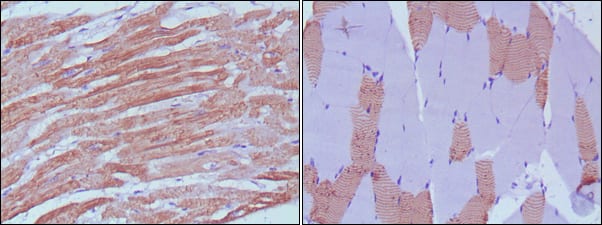

Immunohistochemical analysis of paraffin-embedded human skeletal muscle (left) and cardiac muscle (right) using MYL3 mouse mAb with DAB staining.